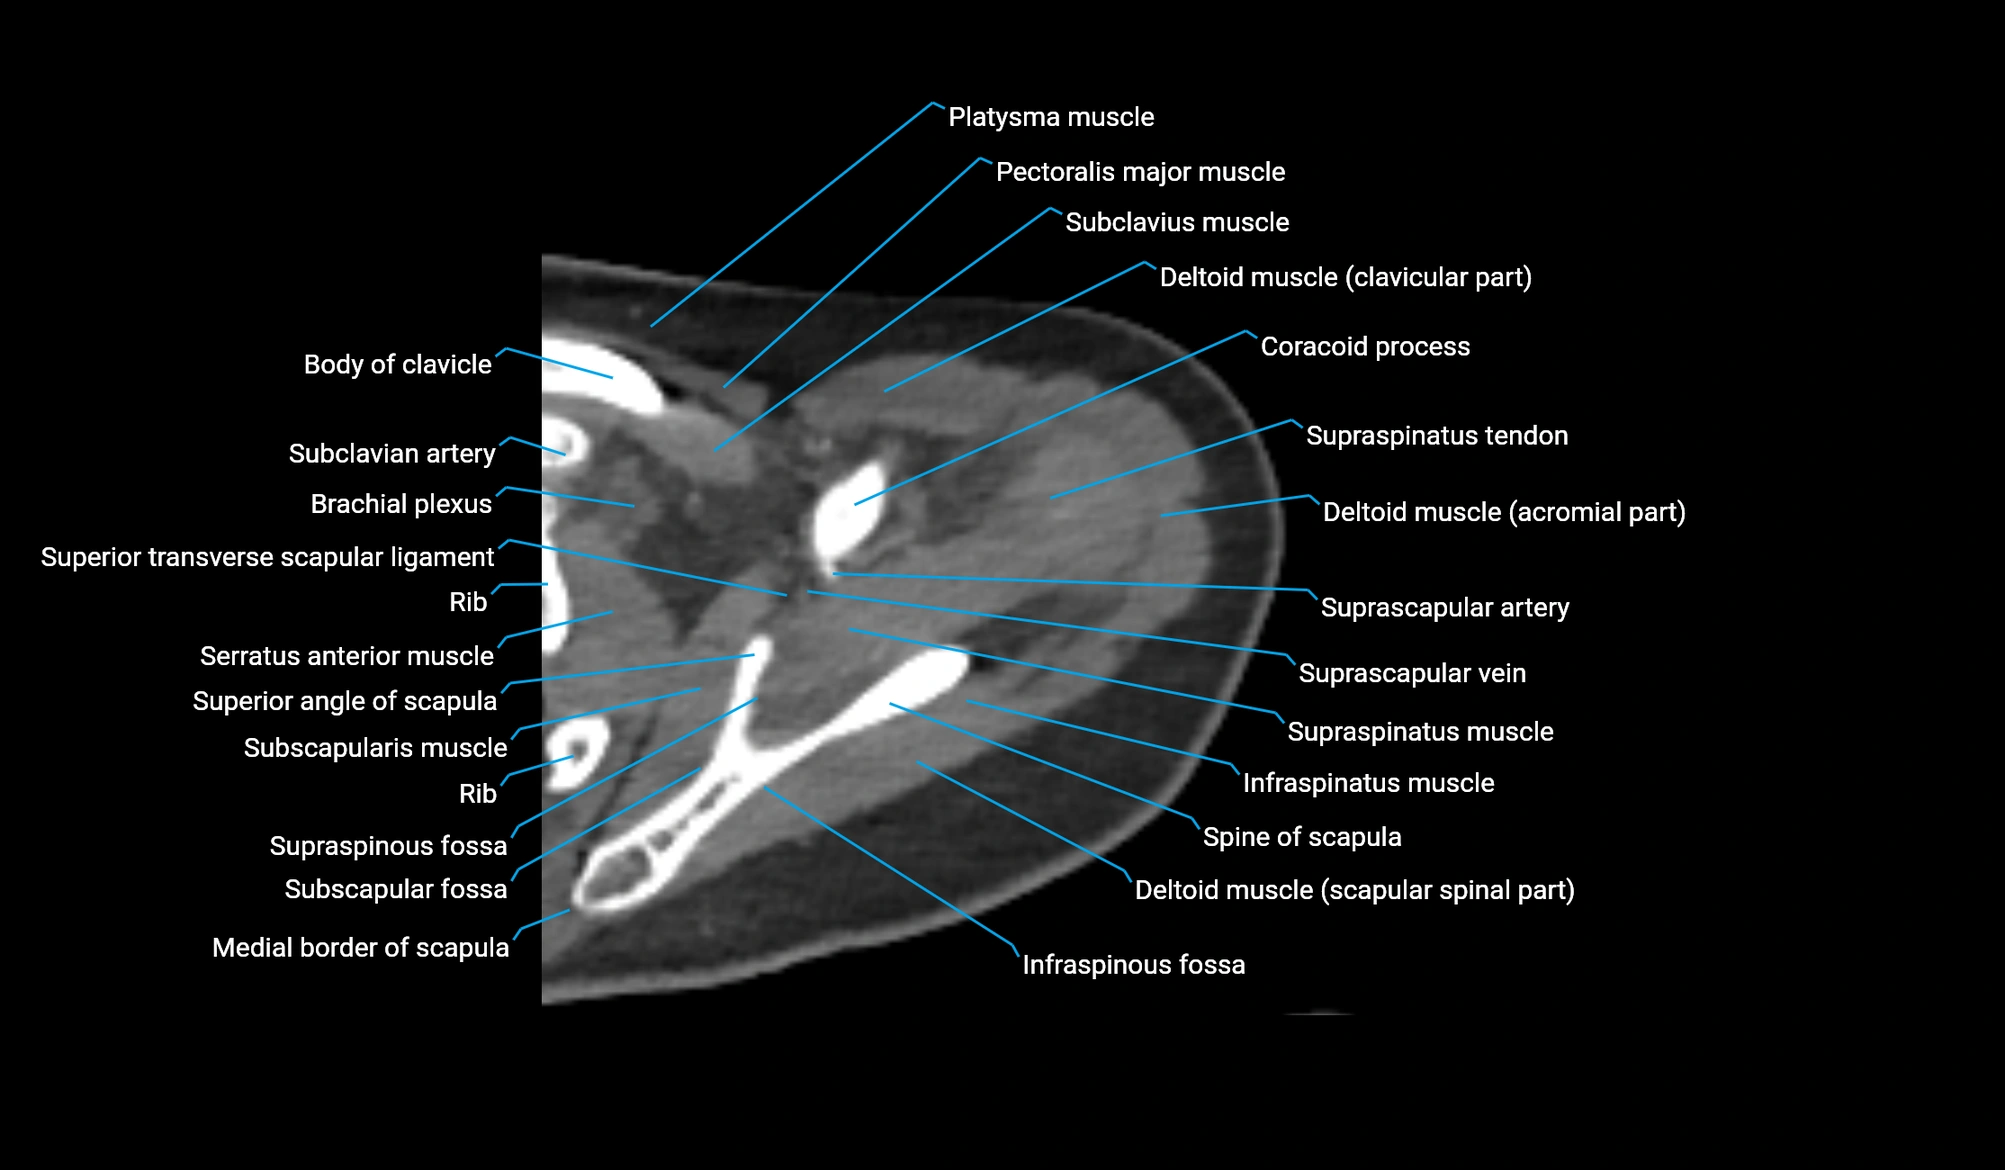

CT image